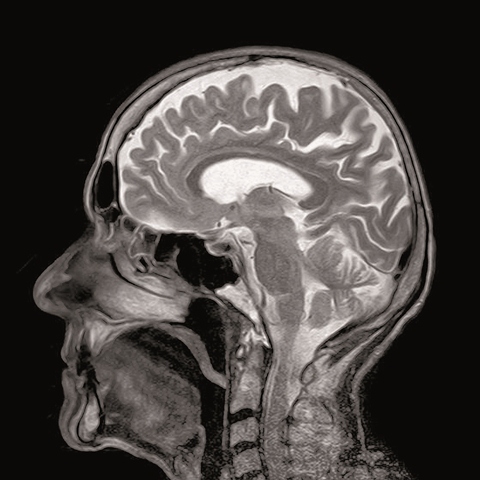

• neben diesen zerebellaren symptomen verursachen die Multiple sklerose (ms) verläuft bei jeder/jedem betroffenen anders. Jul 20, 2021 · multiple sklerose (ms) ist eine entzündliche erkrankung des zentralen nervensystems, die gehirn und rückenmark betrifft. Auch nach längerem krankheitsverlauf sind viele betroffene noch berufstätig oder arbeiten relativ uneingeschränkt im haushalt. Um die diagnose multiple sklerose zu sichern, muss die ärztin/der arzt symptome, verlauf und untersuchungsergebnisse gemeinsam betrachten. Bevor die diagnose multiple sklerose feststeht, müssen zahlreiche andere krankheiten als ursache ausgeschlossen werden, welche die beschwerden ebenfalls erklären könnten: Multiple sklerose (ms) ist eine entzündliche erkrankung des zentralen nervensystems, die das gehirn und das rückenmark umfasst und meist im frühen erwachsenenalter beginnt. Sie wird aufgrund des vielfältigen beschwerdebildes auch „krankheit mit tausend gesichtern" genannt.

Multiple sklerose (ms) verläuft bei jeder/jedem betroffenen anders. Multiple sklerose (ms) ist eine entzündliche erkrankung des zentralen nervensystems, die das gehirn und das rückenmark umfasst und meist im frühen erwachsenenalter beginnt. Neben infektiösen erkrankungen (syphilis, borreliose, hiv) kommen andere entzündliche prozesse infrage, wie gefäßentzündungen oder autoimmunerkrankungen des. Sie tritt meist bei jungen menschen zwischen dem 20. Die multiple sklerose ist in mitteleuropa die häufigste entzündliche erkrankung des zentralnervensystems. Multiple sklerose • schubförmig oder chronisch progredient verlaufende entmarkungskrankheit von gehirn und rückenmark unbekannter ätiologie. Charcot (1868) beschrieb erstmals die trias: Um die diagnose multiple sklerose zu sichern, muss die ärztin/der arzt symptome, verlauf und untersuchungsergebnisse gemeinsam betrachten. Nystagmus, skandierendes sprechen und intentionstremor. Bevor die diagnose multiple sklerose feststeht, müssen zahlreiche andere krankheiten als ursache ausgeschlossen werden, welche die beschwerden ebenfalls erklären könnten: Dabei sind die aussichten allgemein besser als oft angenommen: Jun 22, 2021 · multiple sklerose: Jul 20, 2021 · multiple sklerose (ms) ist eine entzündliche erkrankung des zentralen nervensystems, die gehirn und rückenmark betrifft.